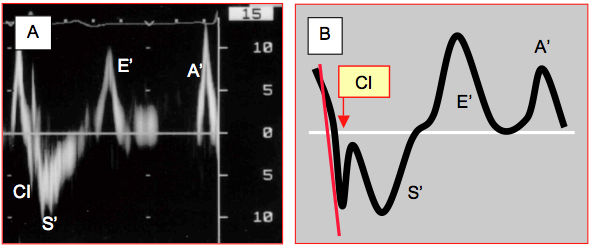

On peut examiner la vélocité de déplacement de l’anneau mitral en plaçant la fenêtre du Doppler pulsé réglé en mode tissulaire (voir Doppler tissulaire) sur sa partie latérale, septale (4-cavités, 0°) ou antérieure (2-cavités, 90°). On y observe une vitesse de déplacement systolique S’ > 8 cm/s au niveau septal et > 10 cm/s au niveau latéral. Ce mouvement est précédé d’un bref pic de vélocité qui représente la contraction isovolumétrique (Figure 25.178) [1]. La quantification de ce dernier mouvement est toutefois imprécise en mode Doppler standard ; la mesure de l’accélération isovolumétrique en mode strain rate est plus fiable (voir Indices myocardiques tissulaires).

Figure 25.178 : Examen au Doppler tissulaire de la vélocité des mouvements systolo-diastoliques de l'anneau mitral dans sa portion latérale. A : image spectrale de la vélocité des mouvements de l'anneau enregistrés dans la fenêtre d'examen; CI: contraction isovolumétrique; S': descente systolique de la contraction éjectionnelle, normalement ≥ 10 cm/s; E’: mouvement protodiastolique; A’: mouvement de la contraction auriculaire en télédiastole. B : représentation schématique de la vitesse de déformation de l'anneau au cours d'un cycle cardiaque (strain rate); le trait rouge est la pente de la contraction isovolumétrique qui permet d'en calculer l'accélération [6].